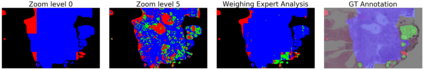

Prevention and early diagnosis of breast cancer (BC) is an essential prerequisite for the selection of proper treatment. The substantial pressure due to the increase of demand for faster and more precise diagnostic results drives for automatic solutions. In the past decade, deep learning techniques have demonstrated their power over several domains, and Computer-Aided (CAD) diagnostic became one of them. However, when it comes to the analysis of Whole Slide Images (WSI), most of the existing works compute predictions from levels independently. This is, however, in contrast to the histopathologist expert approach who requires to see a global architecture of tissue structures important in BC classification. We present a deep learning-based solution and framework for processing WSI based on a novel approach utilizing the advantages of image levels. We apply the weighing of information extracted from several levels into the final classification of the malignancy. Our results demonstrate the profitability of global information with an increase of accuracy from 72.2% to 84.8%.